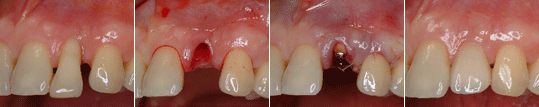

상실된 앞니부위에서 1회법으로 임플란트를 식립하고 회복한 증례

상실된 두 개의 앞니를 2개의 임플란트를 식립하여 회복한 증례

상한 앞니를 발거하고 즉시 임플란트를 식립하여 회복한 증례 임플란트 식립을 위한 골 증대술